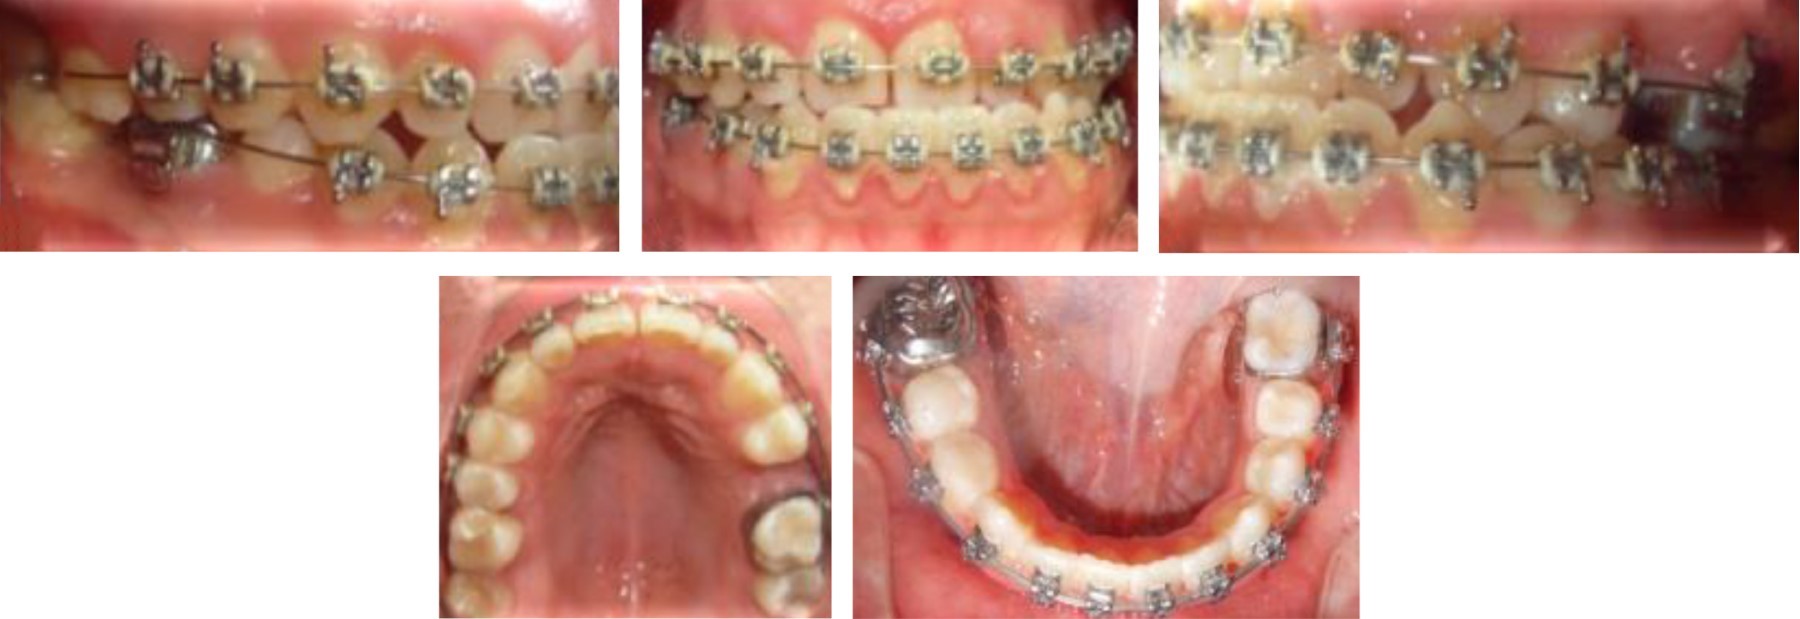

After the extraction of the third molars, we proceeded to the placement of fixed appliance Roth self-ligating slot 0.022" to begin phase I, starting with NiTi 0.014" archwires in both arches to begin with the alignment and leveling (Figure 6).

The treatment continued in the first phase, aligning and leveling, using 0.016" NiTi round archwires, and then begin to express torsional movements with 0.016" × 0.022" NiTi rectangular archwires, and 0.017" × 0.025" and 0.019" × 0.025" NiTi, then the same calibers were used but with a different alloy (stainless steel) (Figure 7).

Figure 7

Figure 8